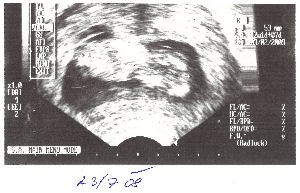

Dneska už maminka konečně dostala těhotenskou průkazku, kam se zapisují např. její váha (díky nevolnostem o 4kg nižší než původní), výška (pořád stejná) :o), tlak (nízký) a následné kontroly a vyšetření, které nás ještě čekají. Pan doktor mě opět prohlédl svým odborným zrakem, tedy přes UTZ (ultrazvuk) a udělal jednu fotečku. Tady mi to moc sluší a už měřím 53mm! To napravo je moje hlavička s obličejíčkem dolu a zbytek tělíčko. Ty světlejší skvrny na tělíčku jsou ručička a nožička.